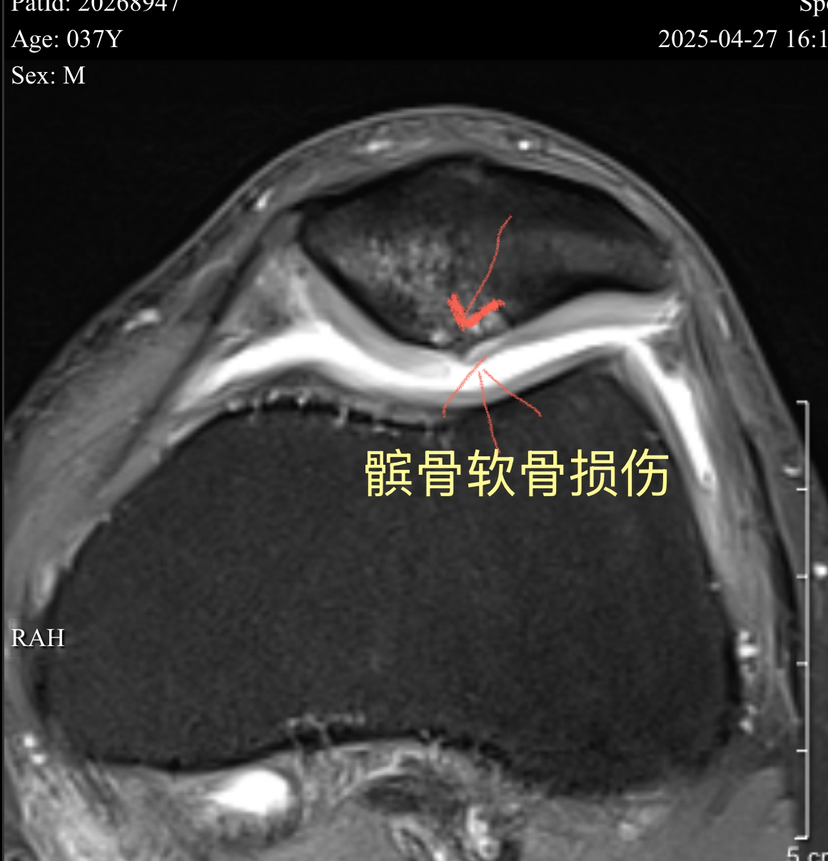

滑车软骨损伤 (软骨剥脱,软骨下骨暴露)

下面展示典型的膝关节软骨损伤,MRI核磁扫描可以清晰发现软骨损伤(3-4度),门诊检查非常常见!